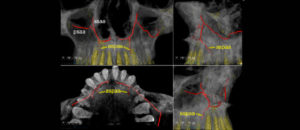

185 – Manejo endodóntico del dens invaginatus Tipo IIIB